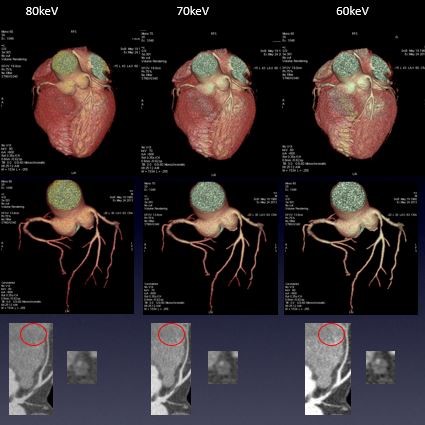

病例资料:患者男性,53岁 扫描参数 模式:GSI -60 AutomA@0.35sec/rot@DC40mm@SFOV Cardiac Large 方式:SnapShot Pulse 造影剂注射方案:350mgI/100ml@50ml@4ml/sec Cardiac GSI:LAD软斑块/远端肌桥能谱工具联合分析 1. 单能量工具:随着keV降低,VR图像血管细节显示更清楚,60keV更好的优化血管显示 2. 能谱曲线:多个感兴趣区分析,纤维斑块为主,其内见脂质髓核,且该脂质髓核靠近血管管腔,故该软斑块考虑为易损斑

3. 碘基物质图像观察:与低keV图像同样能清晰显示血管细节及软斑块内结构的密度差异

4. 碘基物质含量定量分析:碘基值比CT值更敏感反应心肌灌注情况

冠脉能谱成像的应用小结: 单能量工具:低keV优化血管显示。特别对于血管受限无法接受高流速注射的病人提供更多低流速造影剂注射方案,同时可以减少造影剂用量。低keV对显示低密度斑块更加敏感。一些较为模糊的斑块在低能量级别都可以被清晰的显示出来; 能谱曲线:多感兴趣区分析,对斑块成分进行定性分析; 碘基物质图像:更清晰显示血管腔细节; 碘基物质含量定量分析:比CT值更敏感反应心肌灌注情况。